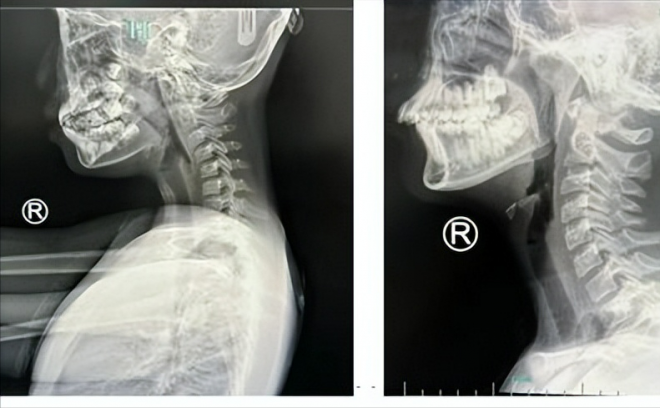

根據《三立新聞》報導,中國浙江省杭州市有一名9歲女童,近日常有脖子痠痛、手指發麻等症狀,嚇得家人趕緊帶她去看醫生,一查才知她身體出大事了!一般來說,正常人的頸椎是「正C形」,但女童的頸椎弧度已經往反方向彎曲,變成「一條直線」,進一步檢查發現她頸椎老化像是50歲老人。